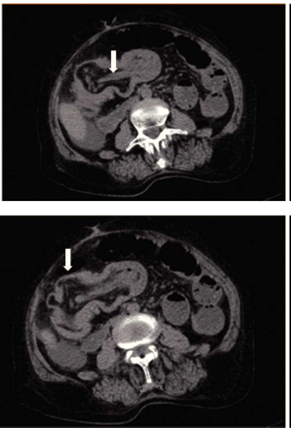

La tomografía computarizada es actualmente la herramienta más confiable para el diagnóstico de los lipomas colónicos; mostrando una tumoración esférica con bordes regulares bien delimitados con densidades de absorción de entre −40 a −120 unidades Hounsfield, compatible con tejido graso.9,12En el caso de la intususcepción intestinal secundaria a lipoma colónico, la tomografía computarizada es el método preferido para el diagnóstico. Reportándose una sensibilidad de 71.4-87.5% y una especificidad del 100% verificada con la cirugía subsecuente.34 A pesar de las herramientas diagnósticas el diagnóstico diferencial con procesos malignos es el principal reto previo al procedimiento quirúrgico.

Se trata de paciente femenino de 77 años de edad, con antecedente de hipertensión arterial sistémica, ingresa a nuestro servicio por presentar cuadro doloroso abdominal intenso de una semana de evolución (fig. 1), acompañado de distensión abdominal náusea y vómito, el cual no remitió con la administración de analgésicos, acudió a valoración por facultativo quien solicitó ultrasonograma (USG) abdominal evidenciando la presencia de un tumor en colon derecho, se ingresó a la paciente por presentar persistencia de la sintomatología. A la exploración física hemodinámicamente estable se encontró abdomen distendido, doloroso a la palpación, superficial, media y profunda en cuadrantes abdominales inferiores y ruidos metálicos a la auscultación, con datos de irritación peritoneal. Paraclínicos con leucocitosis leve únicamente. En el USG abdominal reportó en flanco derecho una imagen ecogénica, redondeada, bien delimitada, con medidas de 41 × 38 × 59 mm en sus ejes mayores, la cual a la aplicación de Doppler color no mostró vascularidad, esta zona es aperistáltica, en relación a conglomerado de asas. No se identifica líquido libre. La TAC abdominal (fig. 2) con imágenes compatibles a oclusión intestinal probablemente secundaria a invaginación intestinal a nivel de ciego y colon ascendente, la cual condicionaba ascitis y neumatosis intestinal leve, además de probable adenoma suprarrenal derecho. Con lo anteriormente mencionado se infiere diagnóstico de invaginación intestinal, por lo cual se programa de urgencia para laparotomía exploradora.